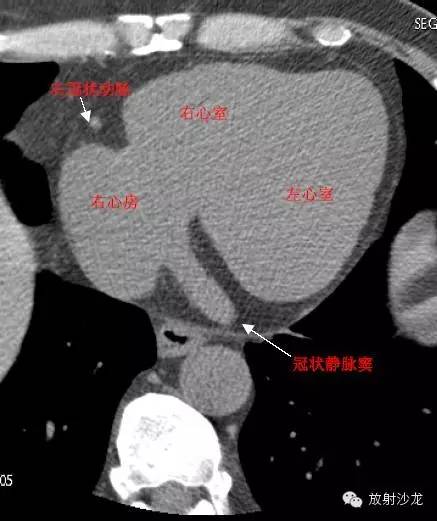

RA -Right Atrium右心房

LV -Left Ventricle左心室

RV -Right Ventricle右心室

LCX -Left Circumflex Artery左回旋支

LAA –Left AtrialAppendage左心耳

CS -Coronary Sinus冠状窦